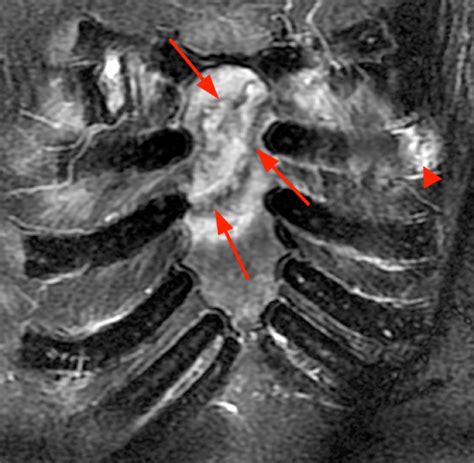

One or more ribs become separated from the costochondral joint (made from cartilage). From the midwestern vascular surgical society. The costochondral separation is a medical condition, in which one of the ribs becomes separated from the sternum.

Costochondral separation happens when your rib tears away from the cartilage that connects it to your breastbone. Osteoporosis, postmenopause, calcium, vitamin d, calcemin, denosumab, fracture, osteopenia, bisphosphonates, osteoblast. Changes in therapeutic principles in fractures of the. Monitoring of fracture calluses with color doppler sonography david a., ostermann p.a., mollenhoff g. Although any of the seven costochondral junctions can become inflamed, the third or fourth ribs are more frequently affected. One or more ribs become separated from the costochondral joint (made from cartilage). For contact athletes, the instability of the rib cage may lead to potential serious complications, similar to rib. L., parsons n., achten j. Been struck by a blunt object; From the midwestern vascular surgical society. Costochondral calcification, osteophytic degeneration, and occult first rib fractures in patient. Costal cartilage fractures are fractures of the cartilage connecting the ribs anteriorly to the sternum. A male patient of 6 years reported with difficulty in mouth opining and inability to take food. Churchill livingstone fifth edition, 2008. Costochondral separation happens when your rib tears away from the cartilage that connects it to your breastbone. Epidemiology there is little published data on costal cartilage fractures. Thoracic trauma may present as an isolated rib fracture, a chest contusion, or a laceration;